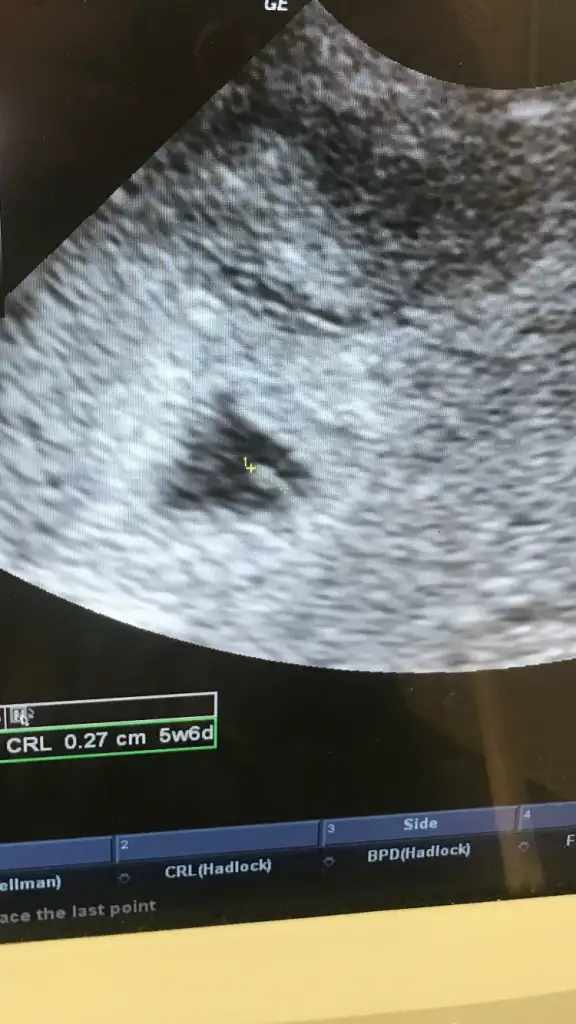

6+3 alttan muayane tek düzgün görüntümüz bu 😂

• A4F50DB8-4197-414C-A6A9-F8FDD74367E9.webp

A4F50DB8-4197-414C-A6A9-F8FDD74367E9.webp

17,6 KB · Görüntüleme: 3.831